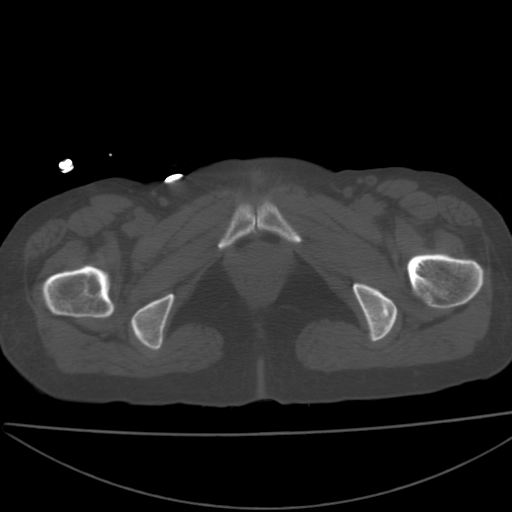

以下是引用xiaoniu在2008-9-6 8:22:00的发言:[br]右侧股骨颈囊性低密度,囊壁边缘硬化,中年妇女,首先考虑:骨囊肿。其次考虑动脉瘤样骨囊肿。[br][br][br][本贴已被 xiaoniu 于 2008-9-6 9:04:54 修改过]